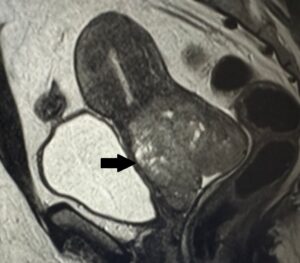

A imagem mostra um câncer de colo uterino localmente avançado (seta). Pensando em boas práticas assistenciais, qual estratégia tem maior potencial para reduzir a ocorrência de casos como este?

Qual estratégia tem maior potencial para reduzir a ocorrência de casos como este?